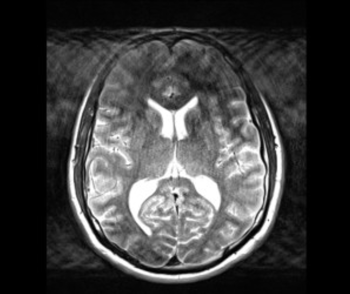

- IV.3.9. Műtermékek